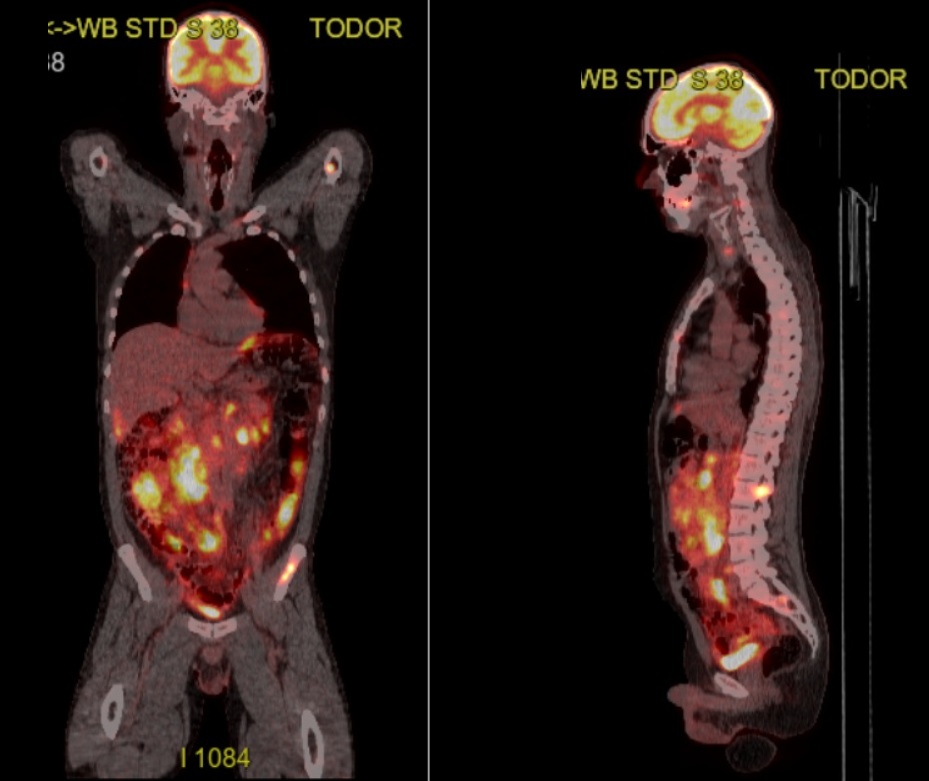

Inainte de internare a aparut si rezultatul de la PET CT (o scanare completa a intregului corp). Inca vestile vin rele, sunt plin peste tot de acumulari si infiltrari ale bolii, stralucesc mai tare ca luminitele de Craciun. Ar trebui sa si dispara mizeriile, asa cum au aparut…ar trebui…

PET CT-ul folosește o substanta, o formă de glucoza marcata radioactiv, iar celulele care consuma multa glucoza apar mai luminoase („stralucesc”) pe imagine. Este cazul celulelor tumorale, mari consumatoare de glucoza, asfel incat, cu exceptia capului, unde creierul are activitate intensa metabolica si in imprejurari normale, sunt invadat de limfom, scor Deauville maxim posibil, 5 din 5, mai bine nu ma gandesc la asta… ☹️

Inainte de cura 4 am facut un alt PET CT. Pana sa primesc interpretarea, m-am uitat pe CD la aceeasi imagine ca la diagnostic. Arata promitator, s-au stins toate “focurile”. Sper ca si interpretarea sa confirme, s-au generat 4500 de imagini, asta e doar una dintre ele.